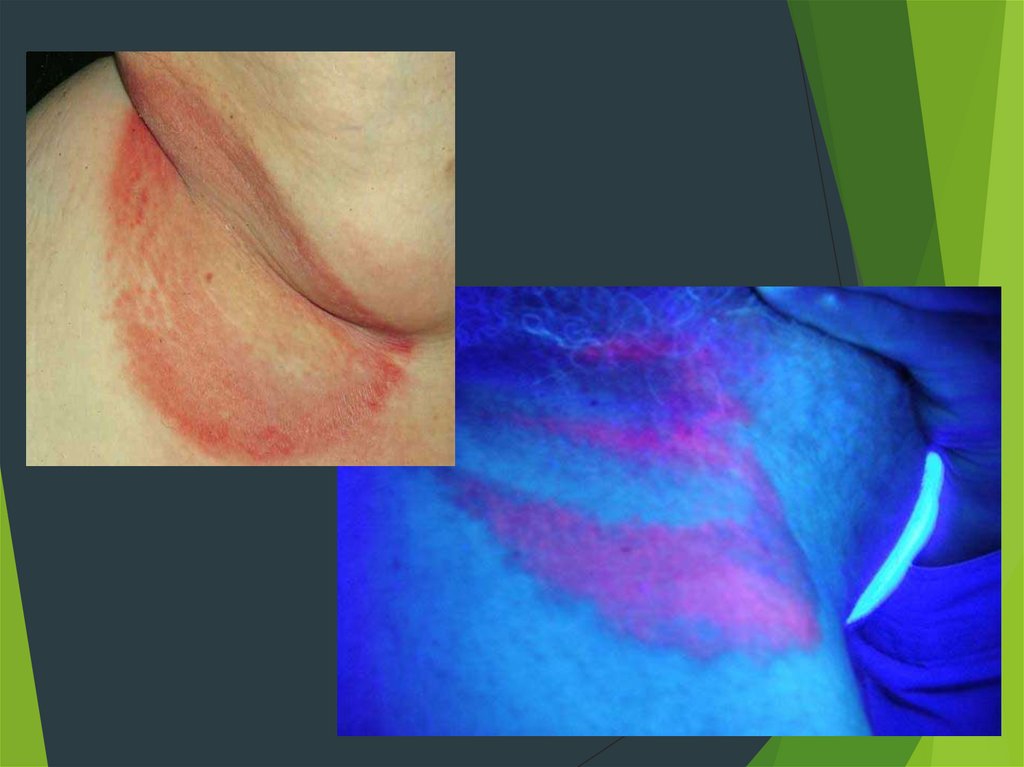

11. Эритразма

1. Поражает роговой слой эпидермиса

2. Локализуется в бедренно-мошоночной

области, подмышечных ямках, под молочными

железами

3. Возникает чаще у потливых и тучных

субъектов

4. Пятна коричневато-красного цвета с резкими

границами

5. Поверхность слегка шелушится

12.

Эритразма

При эритразме поражаются складки кожи.

Первоначально поражения кожи эритразмой четко

определены в виде розовых пятен, покрытых

мелкими трещинками и складками. Позже, пятна от

розового до красного цвета бледнеют, а область

повреждения при эритразме становится коричневой

и шелушится.Решающее значение в диагностике

имеют осмотр очагов в лампе с фильтром Вуда (с

кораллово-красным свечением).